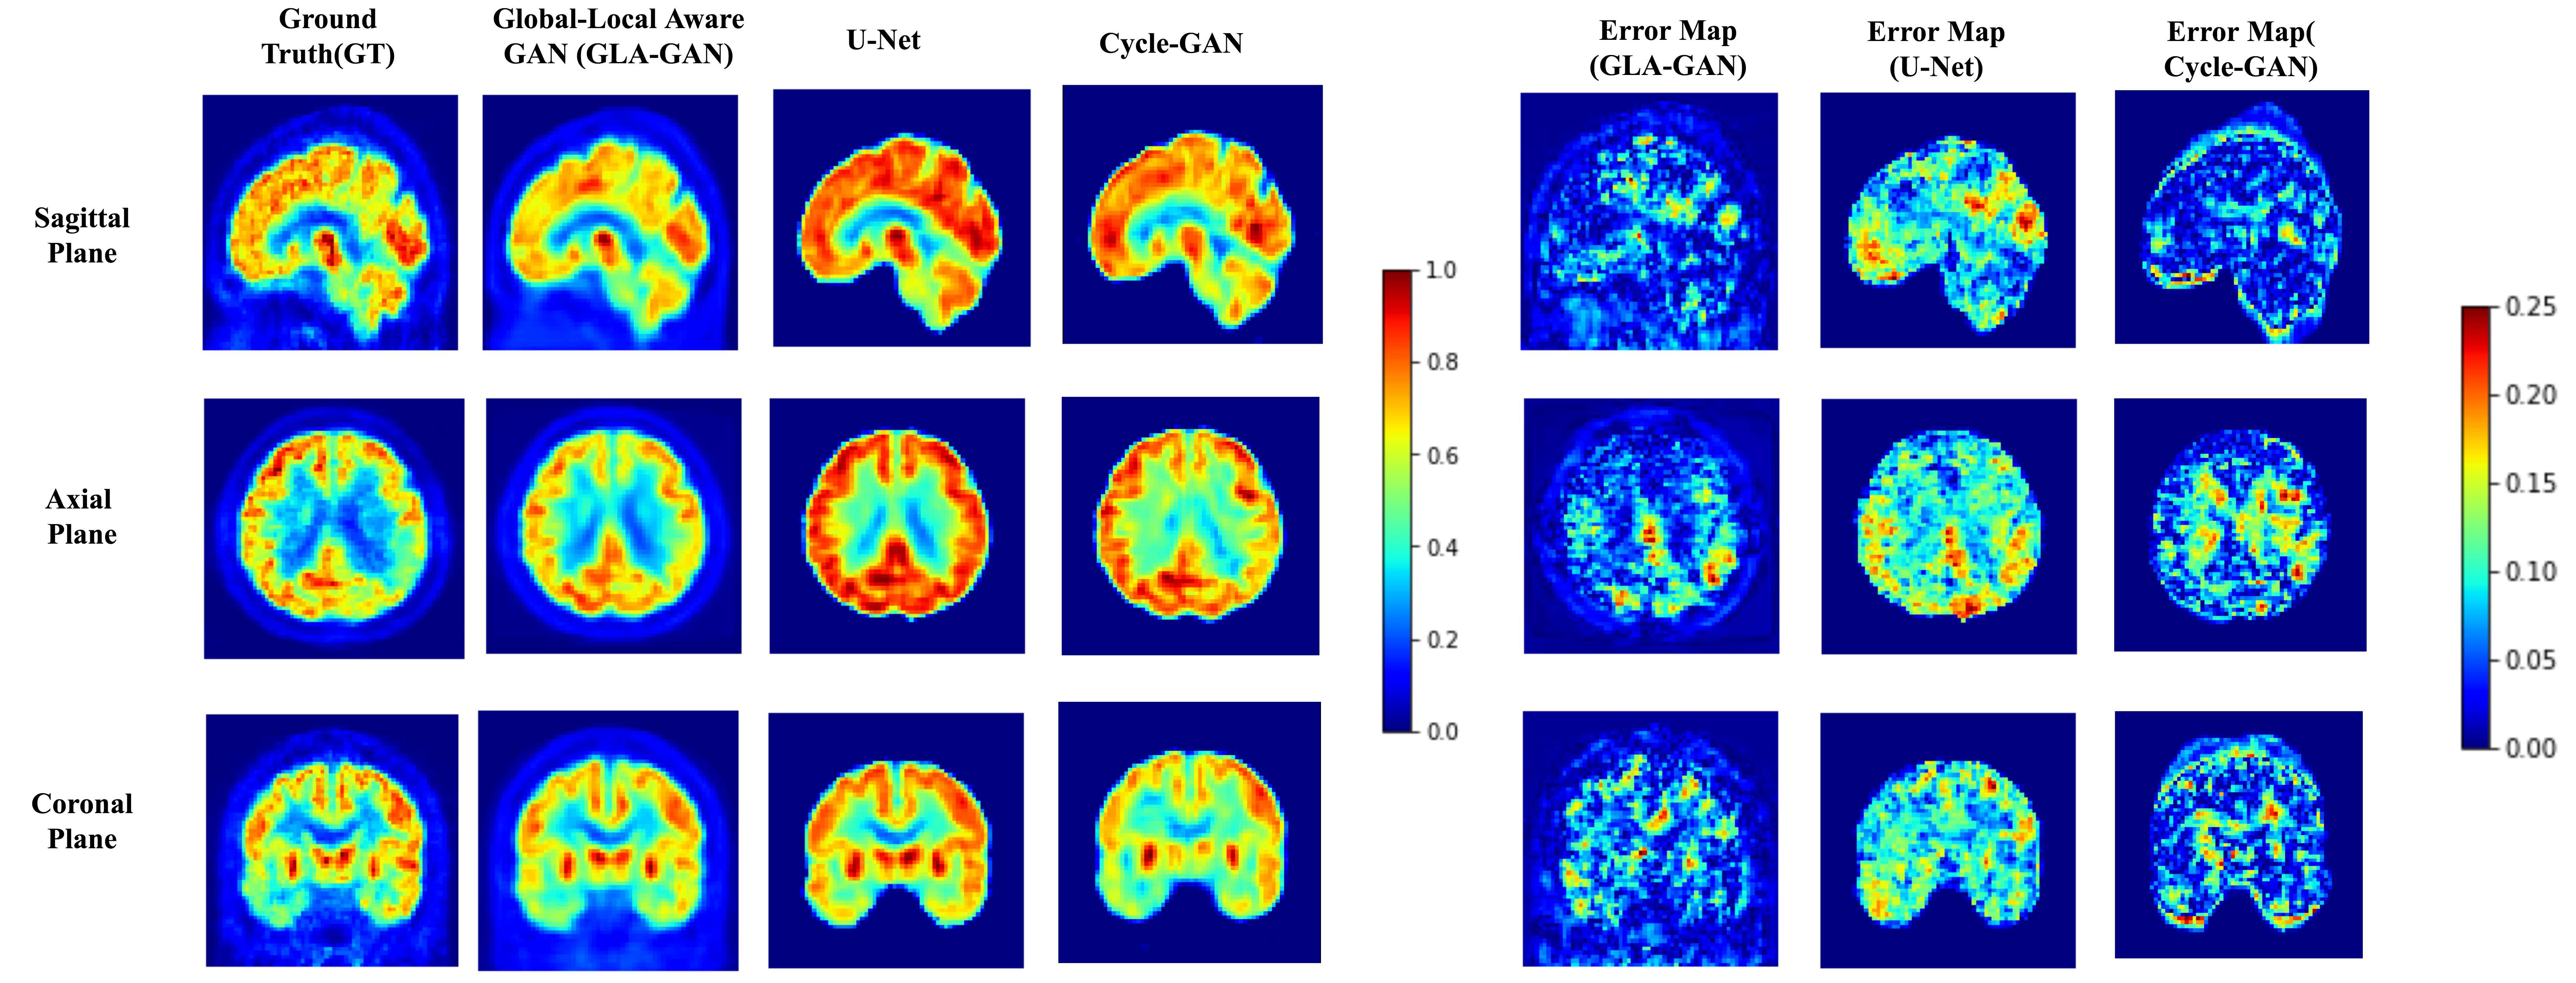

Refer to caption

Figure 2: (a)

Figure 3: (b)

Figure 4: Qualitative comparison of PET scans synthesized using GLA-GAN, Global-GAN and patch based Local-GAN. Ground truth and estimated PET scan along with error maps corresponding to each of the models is presented for an AD (a) and CN (b) sample in axial, coronal and sagittal views. [Best viewed in color]

Firstly, we demonstrate the significance of incorporating both global and local contextual information simultaneously through parallel modules in the GLA-GAN framework. To this end, we compare three variants of the multi-path architecture: (i) Global GAN, (ii) Local GAN and (iii) Global-Local GAN. Figures 4 (a) and (b) show qualitative visualizations of PET scans synthesized using these three models along three planes (axial, sagittal and coronal) for an AD and CN sample respectively. In addition to the generated images, error maps with respect to the ground truth are also presented. Although not readily apparent, there are subtle differences in the estimates generated by the individual Global and Local only modules. A closer observation reveals that while the local module is better at capturing intricate details like the shape of ventricles, the global module achieves better estimate of the FDG uptake intensity. However, it is clearly evident from both synthesized images and error maps that the hybrid model predicts the FDG uptake patterns for both classes of samples (AD and CN) most accurately.